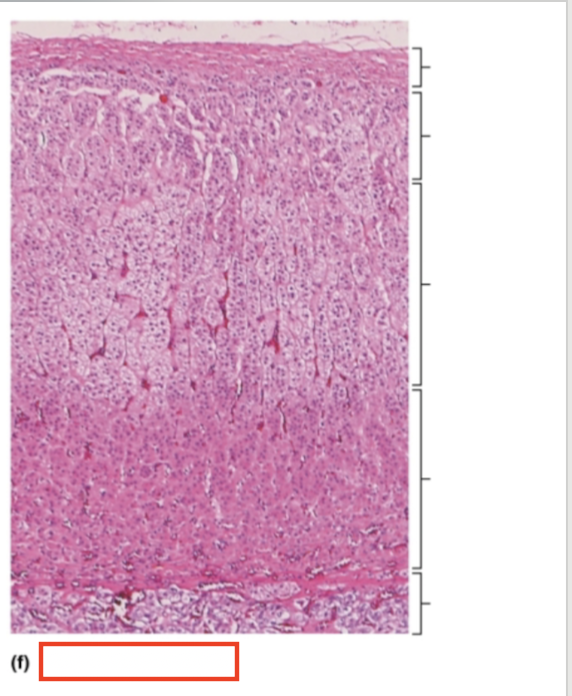

What structure is highlighted?

capsule

What structure is highlighted?

zona glomerulosa

What structure is highlighted?

zona fasciculata

What structure is highlighted?

zona reticularis

What structure is highlighted?

adrenal medulla

What tissue is shown?

adrenal gland